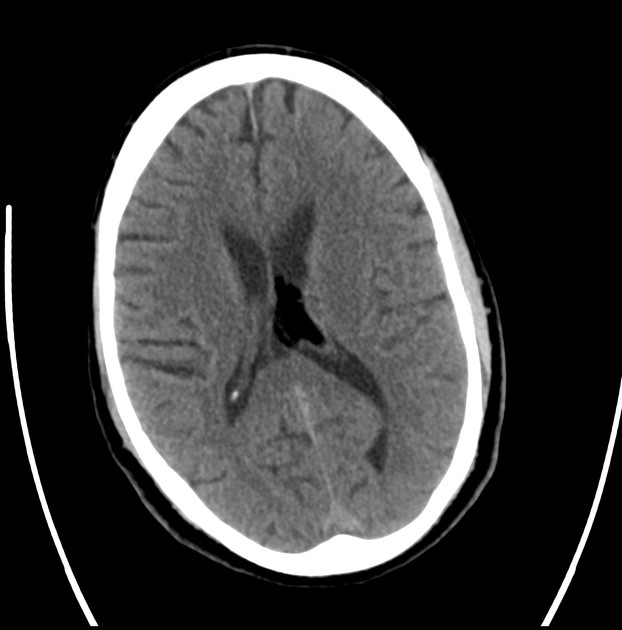

МСКТ при липоме головного мозга выявляет следующие анатомические аспекты:

В нативном режиме определяется гиподенсное образование с чёткими контурами, отсутствие перифокального отёка, возможное расположение в области мозолистого тела, межполушарной щели или супратенториального пространства, однородная структура с низкой рентгеновской плотностью, характерной для жировой ткани.

В режиме сканирования мягких тканей визуализируется изоденсное с жировой тканью образование, отсутствие структурных изменений окружающих тканей, возможное сдавление прилежащих сосудов, отсутствие кальцификаций или некротических зон.

В режиме с контрастированием выявляется отсутствие накопления контраста в липоматозных структурах, возможное наличие капсулы вокруг образования, отсутствие инфильтративного роста, чёткое разграничение с окружающими тканями.